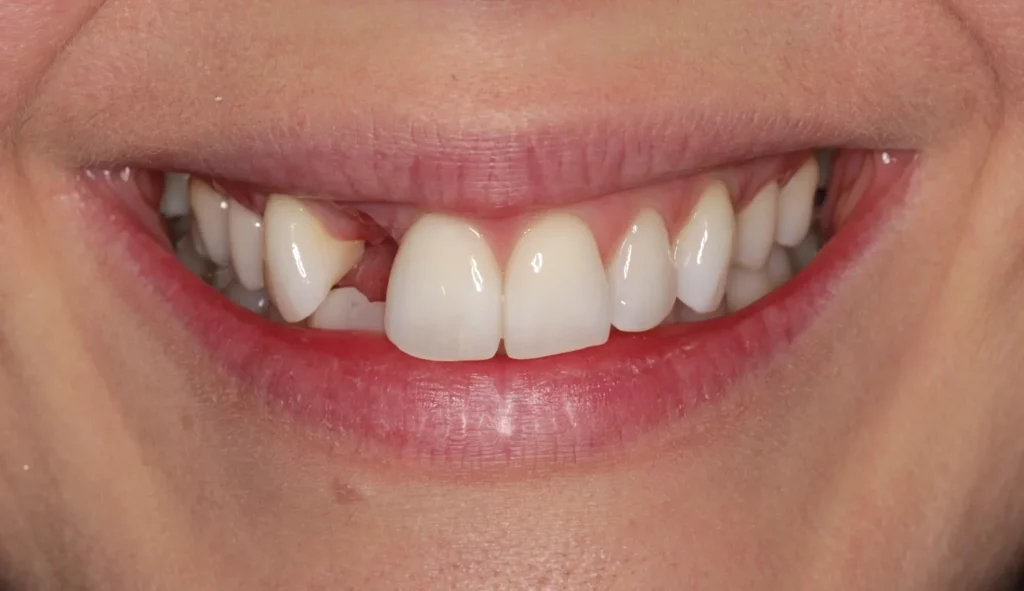

This lady was very upset after a dumbbell hit her mouth in the gym and knocked the front tooth out.

A temporary bridge was made to avoid her having to wear a temporary denture during the teatment, which is less comfortable.

A single implant with bone grafting was placed.

Once the implant was bedded into the bone, a new porcelain crown was fitted on the implant, and a new crown was placed on the adjacent tooth to match in better.